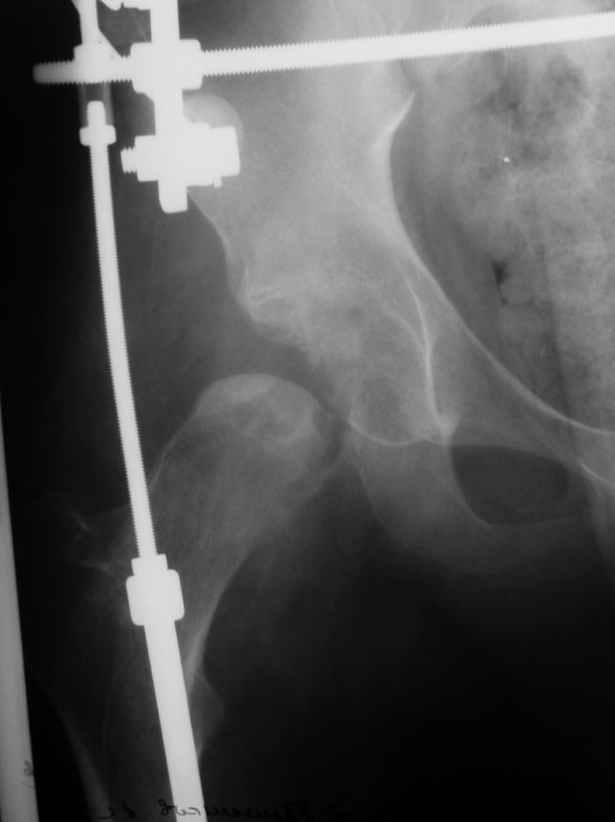

Здравствуйте. К нам поступил мальчик 15 лет с застарелым 7-месячным вывихом бедра из области. Травма мотоциклетная, при поступлении в больницу по месту жительства диагностирован перелом диафиза бедра и не распознан вывих бедра с этой же стороны.

Бедро было синтезировано пластиной и успешно срослось. Как поступить сейчас с вывихом? По КТ видны интерпонированные отломки, впечатление что это фрагменты головки бедра. Поделитесь, пожалуста, опытом. Спасибо.